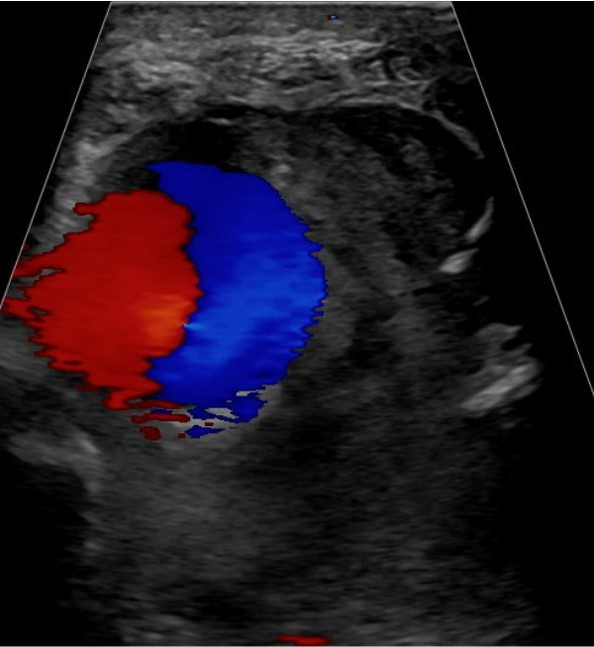

Figure 1: (a) Pre-operative radiograph reveals acute, mildly comminuted fractures of the mid/distal tibia and proximal fibular shaft. (b) Post-operative radiograph reveals intramedullary nailing of tibial shaft fracture in improved alignment and proximal fibular shaft fracture with increased displacement and apex posterior angulation. Upon the present presentation with the increased lateral calf pain and swelling, Doppler ultrasound revealed a large pseudoaneurysm of the ATA with the characteristic yin-yang sign (Fig. 2). CTA confirmed a pseudoaneurysm arising from the proximal ATA, surrounded by a large hematoma in the leg (Fig. 3). The largest aneurysmal sac measured approximately 8.7 × 10.4 × 16.1 cm, with an actively filling, non-thrombosed component measuring about 3.4 × 3.8 × 6.5 cm. Given the significant compressive symptoms caused by the hematoma, coil embolization of the ATA was performed to exclude blood flow into the pseudoaneurysm cavity. Selective catheterization of the left ATA was achieved through ultrasound-guided puncture of the right common femoral artery. Multiple Penumbra Ruby coils were deployed into the proximal and distal segments of the ATA, effectively sealing the pseudoaneurysm defect. A pre- and post-procedural angiogram demonstrated successful cessation of blood flow into the pseudoaneurysm cavity (Fig. 4a and b).

Figure 2: Color Doppler ultrasound shows a large, rounded structure with a classical yin-yang sign arising from the region of the anterior tibial artery.

Intramedullary nailing with interlocking screws is a reliable method for managing tibial fractures, with a low incidence of complications. Vascular complications, specifically pseudoaneurysm of the ATA following lateral-to-medial distal locking of an intramedullary nail for tibial shaft fractures, were first reported by Han et al., in 2004, with a few additional cases documented since then [1,2,4,5,6]. A pseudoaneurysm can develop in any artery but is most commonly seen in the femoral artery, particularly following cardiac catheterization. It occurs due to an injury to the adventitial layer of the artery, leading to the gradual leakage of blood into the surrounding tissue. Unlike a true aneurysm, which involves all three layers of the arterial wall, a pseudoaneurysm is characterized by a fibrous pseudocapsule that encases the leaking blood [1,8]. Although the exact timing of pseudoaneurysm formation is uncertain, we hypothesize that it likely occurred during drilling or the early phase of proximal interlocking screw fixation, with gradual enlargement over time. The growth rate of a pseudoaneurysm can vary widely depending on factors such as its etiology, anatomical location, and surrounding tissue. In smaller pseudoaneurysms, typically those measuring <3 cm, spontaneous thrombosis may occur, potentially leading to resolution without the need for intervention [7]. Symptoms of a pseudoaneurysm primarily arise from swelling and the mass effect exerted on surrounding nerves and vessels, causing pain, numbness, and muscle weakness [4]. Typically, most superficial pseudoaneurysms present as a painful, pulsatile mass and are relatively easy to diagnose. In contrast, deep pseudoaneurysms, as in this case following tibial nailing, are rare and often overlooked. They can be concealed by expected post-operative edema and soft tissue swelling. In this patient, the swelling and stiffness were initially attributed to normal healing after extensive cutaneous and soft tissue injury, delaying diagnosis and treatment. Doppler ultrasound is the preferred initial screening tool for assessing potential vascular and soft tissue complications. In this case, it revealed an ATA pseudoaneurysm with the characteristic “yin-yang” sign, indicating bidirectional blood flow within the pseudoaneurysm sac. These findings were subsequently confirmed by CTA. Various treatment options are available for pseudoaneurysms, including open surgery with arterial repair, reconstruction, or ligation, as well as minimally invasive methods such as ultrasound-guided compression, thrombin injection, and endovascular interventions such as stenting, coiling, or embolization. While surgical repair and endovascular stenting are typically reserved for pseudoaneurysms arising from large arteries, coiling is preferred for pseudoaneurysms of smaller arteries [8,9,10,11]. A review of the literature shows that management approaches for ATA pseudoaneurysms associated with tibial nailing have varied. Reported cases include non-invasive treatment with ultrasound-guided thrombin injection [6], coil embolization [3], and ATA embolization with coils following surgical hematoma evacuation [4]. Several other cases were managed surgically [1,2,5]. In the present case, the neck of the pseudoaneurysm was successfully closed using coiling as a minimally invasive and effective method. Because of the mass effect and neurovascular compression from the large thrombus, suction and manual evacuation were performed through a small leg incision.